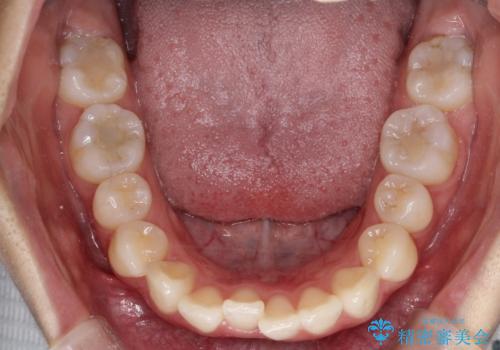

前歯のがたがたを綺麗にしたい

- 前歯がねじれていること、出ていることを主訴に来院されました。

前歯の突出感も改善され、満足していただきました。